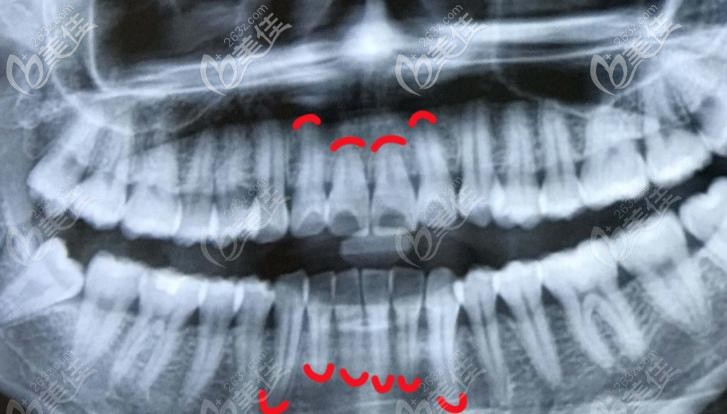

為了進一步加強牙周診療的技術,福州登特口腔特別舉辦了“標準化的牙周刮治”技術交流大會,讓更多人的醫(yī)護人員以及顧客了解牙周病的發(fā)生原因、治療方法以及如何預防。